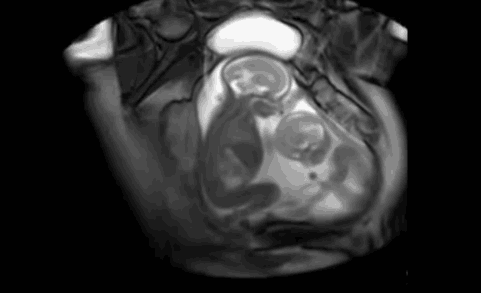

小baby不依不饶,继续战斗!大baby好像开始说话了,猜猜他在说什么呢?

小baby的攻击再次被大baby挡回,不过依然玩得不亦乐乎,毫无停下来之意。